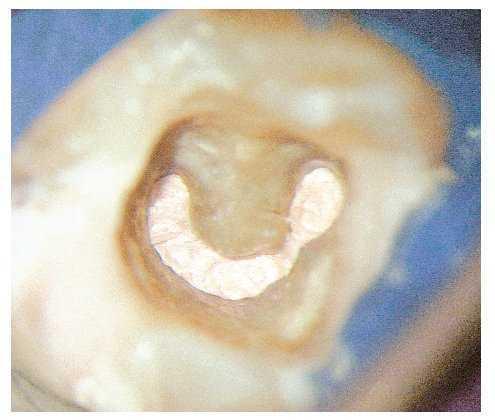

Figura 4a. La radiografía diagnóstica muestra una obturación con sellado marginal en sentido mesiodistal.

Figura 4b. Situación clínica después de retirar la prótesis que necesitaba ser rehabilitada: el conducto radicular muestra un tramo largo ovalado en sentido vestibulolingual, lo que no se reflejó en la radiografía. El cono central existente sólo ocupa una pequeña parte del conducto radicular en sentido horizontal. Se observan algunos restos de sellador y mucho tejido necrótico en la luz residual.